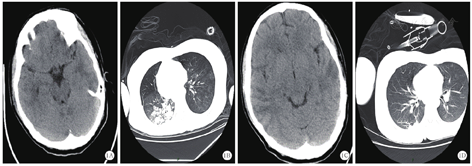

患者不能完全排除自身免疫性脑炎,转入ICU后,给予阿昔洛韦抗病毒、甘露醇脱水降颅压、乙酰谷酰胺营养脑细胞、静脉注射人免疫球蛋白和甲泼尼龙琥珀酸钠调节免疫、丙戊酸钠和左乙拉西坦控制癫痫等综合治疗。入院第4天,患者心率偏慢,最慢为40次/min左右,考虑存在自主神经功能紊乱,给予心宝丸及环磷腺苷葡胺提升心率;约4 d后心率逐渐恢复至75~120次/min,停用心宝丸和环磷腺苷葡胺。入ICU后仍间断出现癫痫发作,加用拉莫三嗪和苯巴比妥控制癫痫发作。入院第7天,患者血清及脑脊液自身免疫性脑炎相关抗体检测为阴性,脑脊液病原微生物基因组检测提示:猫立克次体感染(检出序列数261)。考虑患者存在立克次体感染可能,停用甲泼尼龙琥珀酸钠,给予盐酸米诺环素胶囊及甲磺酸左氧氟沙星氯化钠抗感染。入院第10天,患者间断出现呼吸暂停,伴有血氧饱和度下降,给予经口气管插管,呼吸机辅助呼吸。入院第12天,复查颅脑CT未见明显异常(图1A);胸部CT显示双肺多发高密度影,右肺上下叶部分支气管欠通畅,考虑感染性病变(图1B)。考虑患者肺部感染较重,给予头孢哌酮舒巴坦钠抗感染。入院第14天,复查脑脊液为无色清亮液体,压力约为217.6 mmH2O;脑脊液常规、蛋白未见明显异常。入院第15天和第16天,分别组织全院病例讨论及解放军总医院远程会诊,主要诊断考虑癫痫持续状态(难治性)、重症脑炎,脑炎性质考虑立克次体感染,不除外病毒感染,继续抗立克次体、抗病毒、丙种球蛋白抑制免疫反应、控制癫痫发作等治疗。入院第22天,第二次腰穿送检脑脊液病原微生物基因检测未再检测出猫立克次体。于当日复查颅脑CT显示双侧颞顶叶多发条片状稍低密度影,提示有脑炎可能(图1C);胸部CT显示双肺多发高密度影,右肺下叶部分支气管欠通畅,提示较前明显好转(图1D)。继续给予阿昔洛韦抗病毒,米诺环素及甲磺酸左氧氟沙星氯化钠抗立克次体治疗。入院第23天,拔除气管导管,患者呼吸平稳。入院第25天,患者出现皮疹,皮肤科会诊考虑:过敏性皮炎,重症多形性红斑?(药物引起可能性大)。给予甲泼尼松龙琥珀酸钠注射液60 mg静脉滴注,再次给予人免疫球蛋白0.4 g·kg-1·d-1静脉滴注,连用5 d。入院第27天起,患者的意识逐渐转清,可下床活动,能够配合指令完成动作,未再出现肢体抽搐。入院第32天,第3轮丙种球蛋白治疗结束,当日完善颅脑磁共振成像(magnetic resonance imaging,MRI)检查显示双侧额顶颞岛叶异常信号,考虑炎症,建议治疗后复查;右侧横窦、乙状窦较对侧纤细,考虑发育变异(图2)。入院第33天,患者转回普通病房,意识清,无头痛,无发热,颜面部及颈前皮疹较前减轻,四肢活动基本正常。入院第46天,患者好转出院,出院时意识清,问话对答切题,未见新发皮疹,四肢肌力5级,双侧巴宾斯基征阴性。出院4个月后,患者再次出现癫痫发作,复查颅脑MRI显示双侧额顶颞岛叶异常信号基本吸收、消失,脑部MRI增强未见异常强化(图3)。继续口服左乙拉西坦片,未再出现癫痫发作。